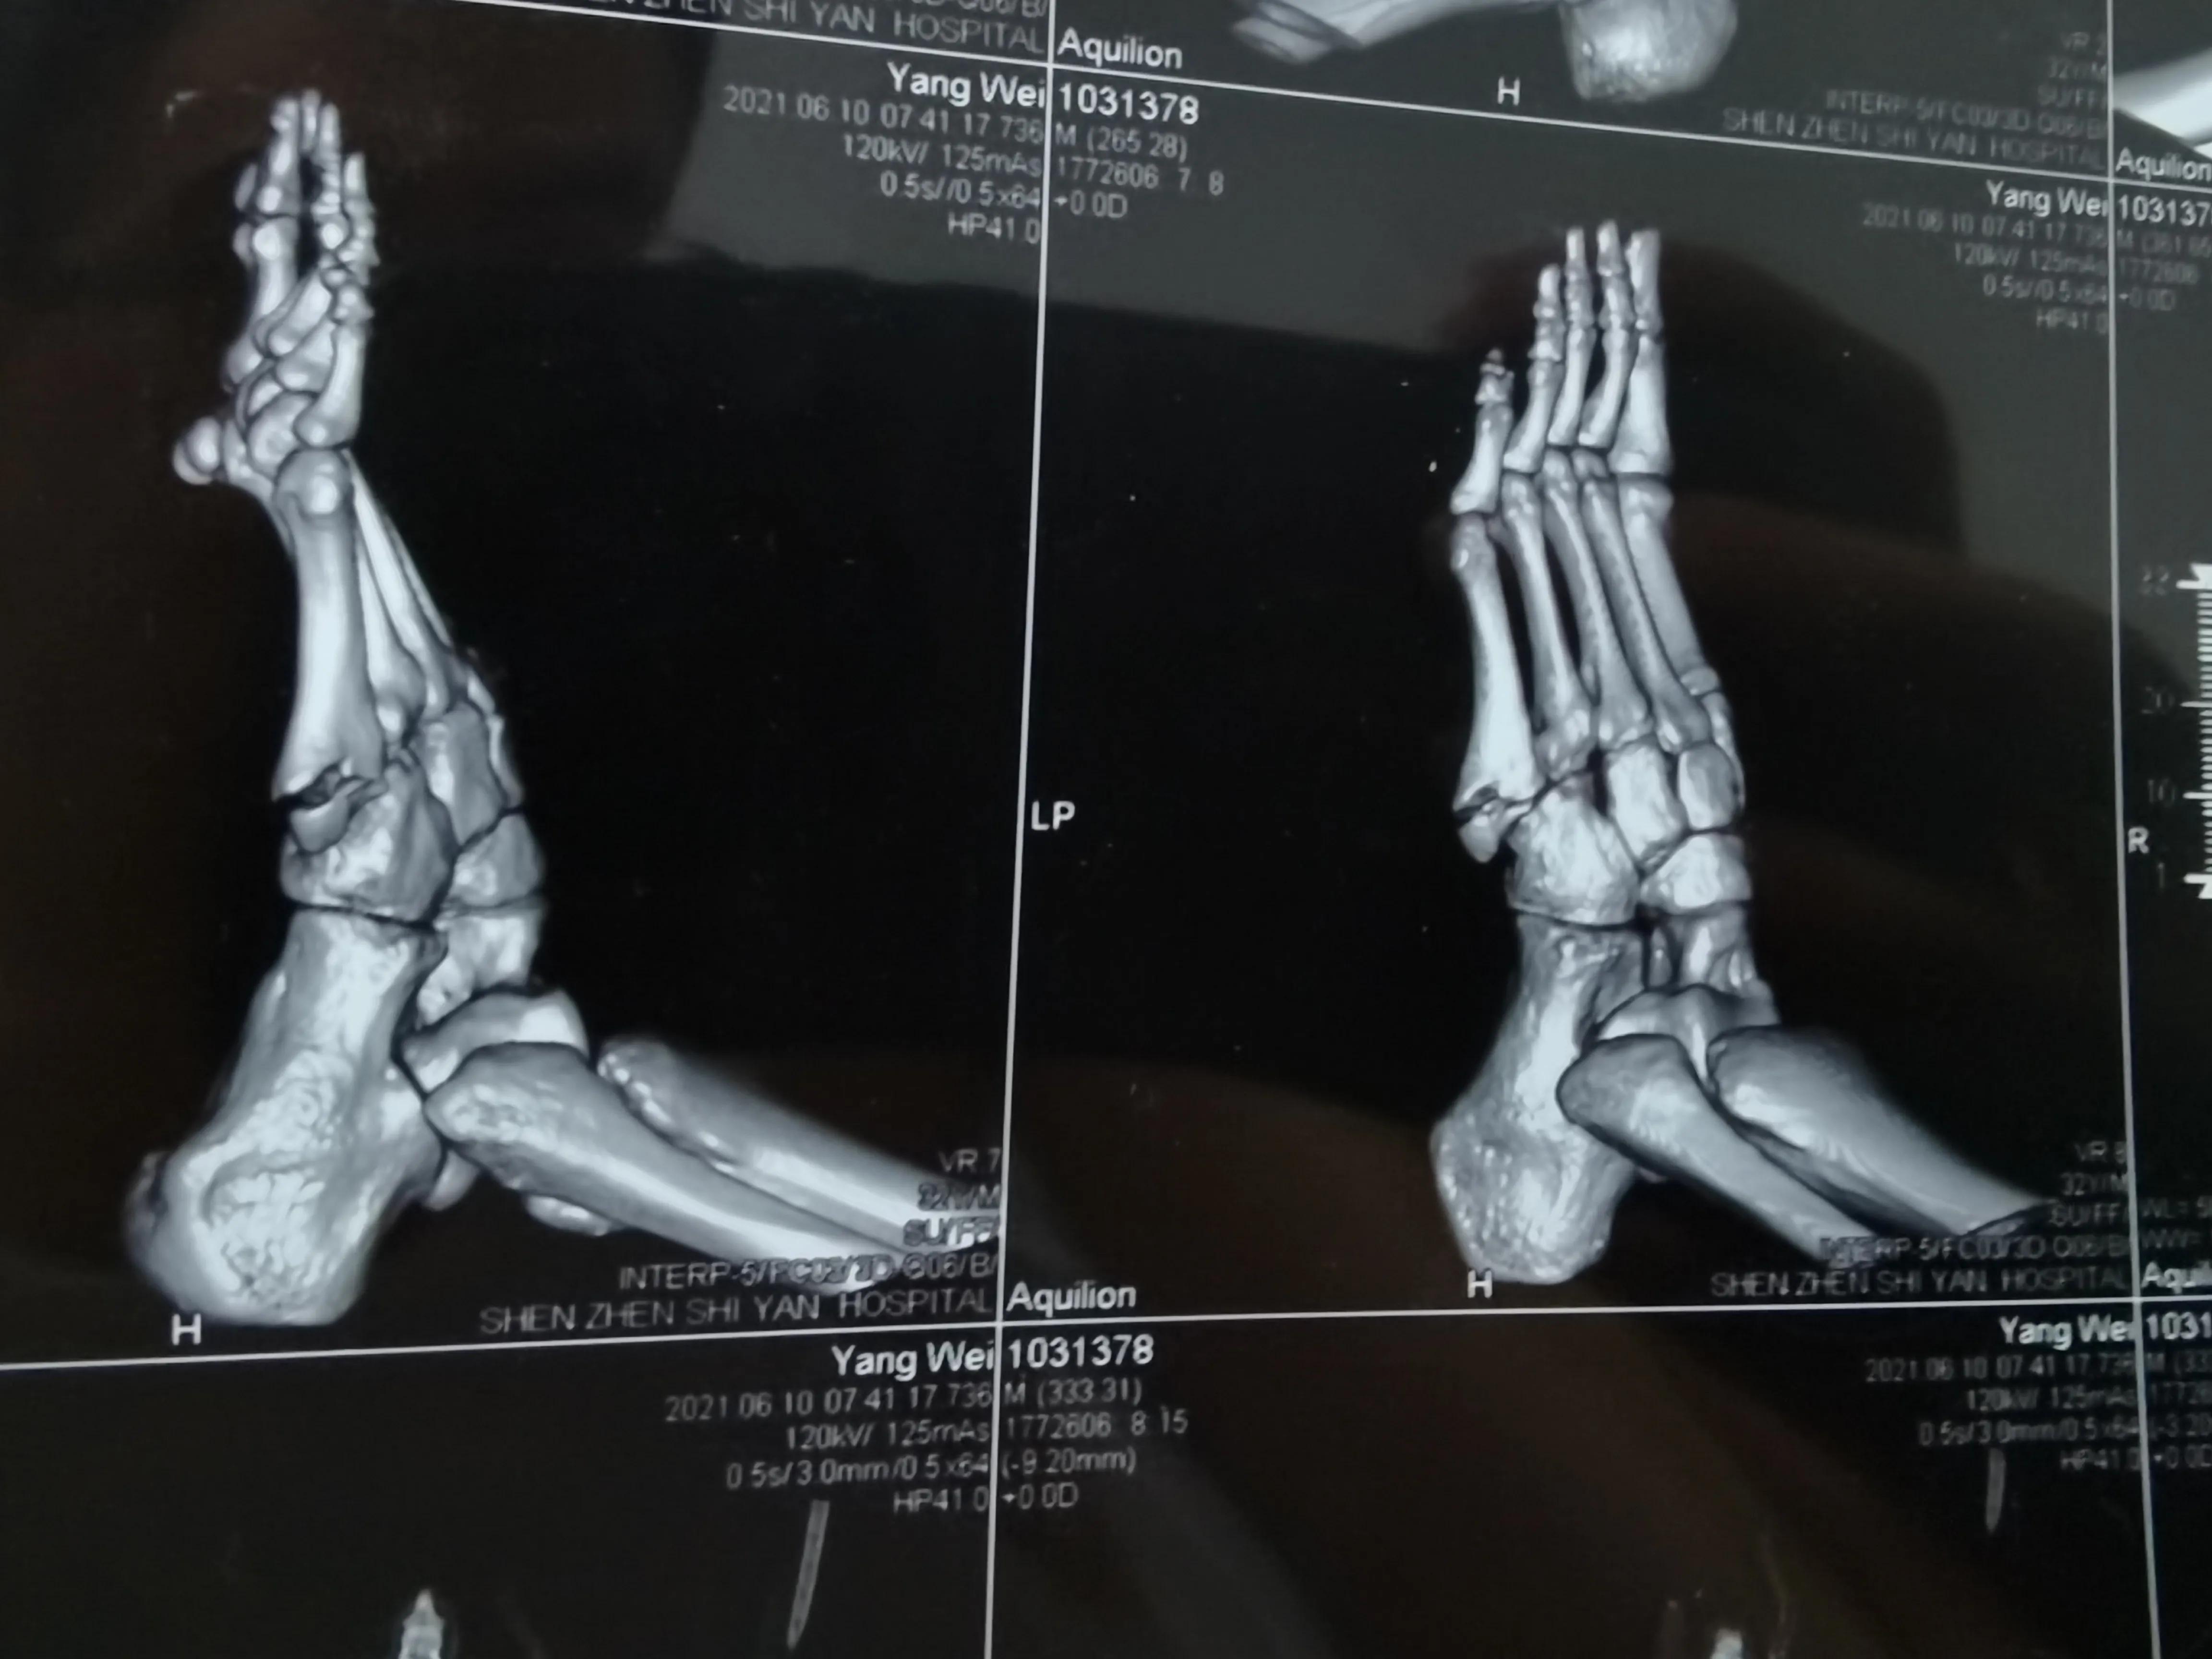

看片子骨缝比较大了,有点移位,而且中间崩碎了一块,一直找不到,后来复查才发现那个碎片掉落在骨缝当中了

此图可以看见中间碎片在骨缝里面